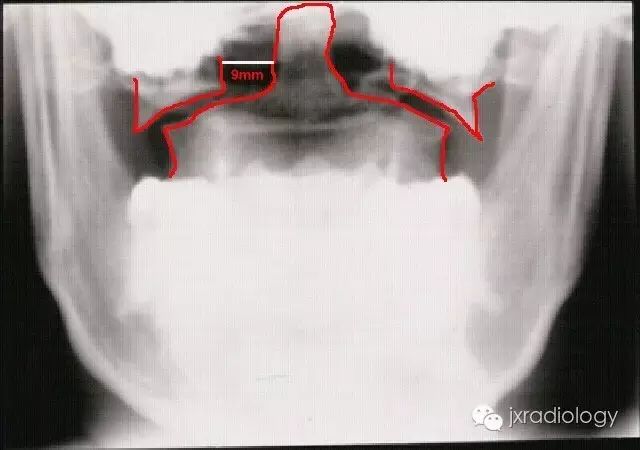

寰椎骨折又名Jefferson骨折(因由Jefferson于1920年首次报道,故此命名)。环形的寰椎遭受轴向压缩和头部向后、下转伸时,暴力经枕骨髁作用于寰椎侧块,并引起寰椎骨环爆裂(散)骨折。寰椎的前弓与后弓双侧骨折,以致侧块被挤压而向四周分离

主要介绍颈椎开口位的X线平片表现:开口位可发现寰椎左右增宽,且与齿突的距离双侧常呈不对称状。如双侧侧方移位总和超过7mm者,则表示寰椎横韧带断裂、寰椎骨折。

正位与齿状突对比似双侧开门样增宽,为此加深记忆,故得此名,如有不妥,敬请谅解(小编)。